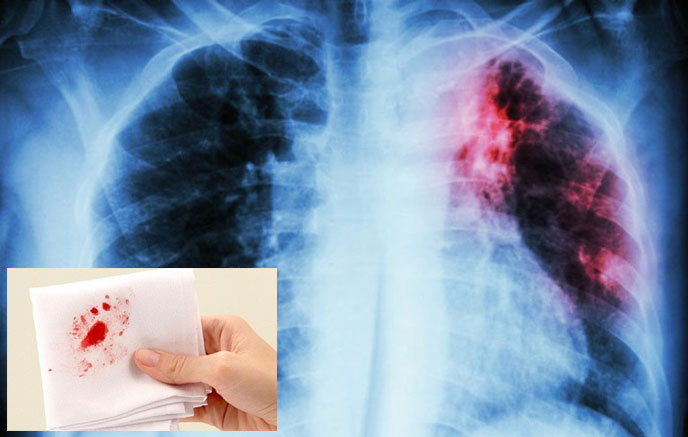

ung thu phoi ho ra mau Ho ra máu là dấu hiệu cảnh báo ung thư phổi đã tiến triển nặng

Ung thư phổi ho ra máu là dấu hiệu thường gặp ở bệnh nhân giai đoạn nặng. Vì vậy, khi có biểu hiện này, người bệnh không được chủ quan.

Ho ra máu là tình trạng khạc ra máu, có thể là lẫn sợi máu trong dịch, đờm hoặc ho ra máu tươi. Tùy vào tình trạng bệnh mà mức độ ho ra máu sẽ nặng nhẹ khác nhau.

Ung thư phổi ho ra máu là dấu hiệu nguy hiểm bởi giai đoạn đầu của bệnh thường không có triệu chứng. Khi đã xuất hiện tình trạng ho ra máu thì bệnh đã tiến triển nặng. Trong khi đó, ung thư phổi lại là bệnh ung thư vô cùng nguy hiểm, có tỷ lệ tử vong cao. Ở nước ta, ung thư phổi là bệnh ung thư phổ biến nhất ở nam giới và đứng thứ 3 trong các loại ung thư ở nữ giới.

Biểu hiện của ung thư phổi ho ra máu là máu thường có màu đỏ tươi hoặc hồng, kèm bọt hoặc sủi bọt do lẫn chất nhầy, đờm hoặc không khí. Kèm theo đó là tình trạng khó thở thường xuyên, thở khò khè, đau ngực, mệt mỏi và suy nhược.